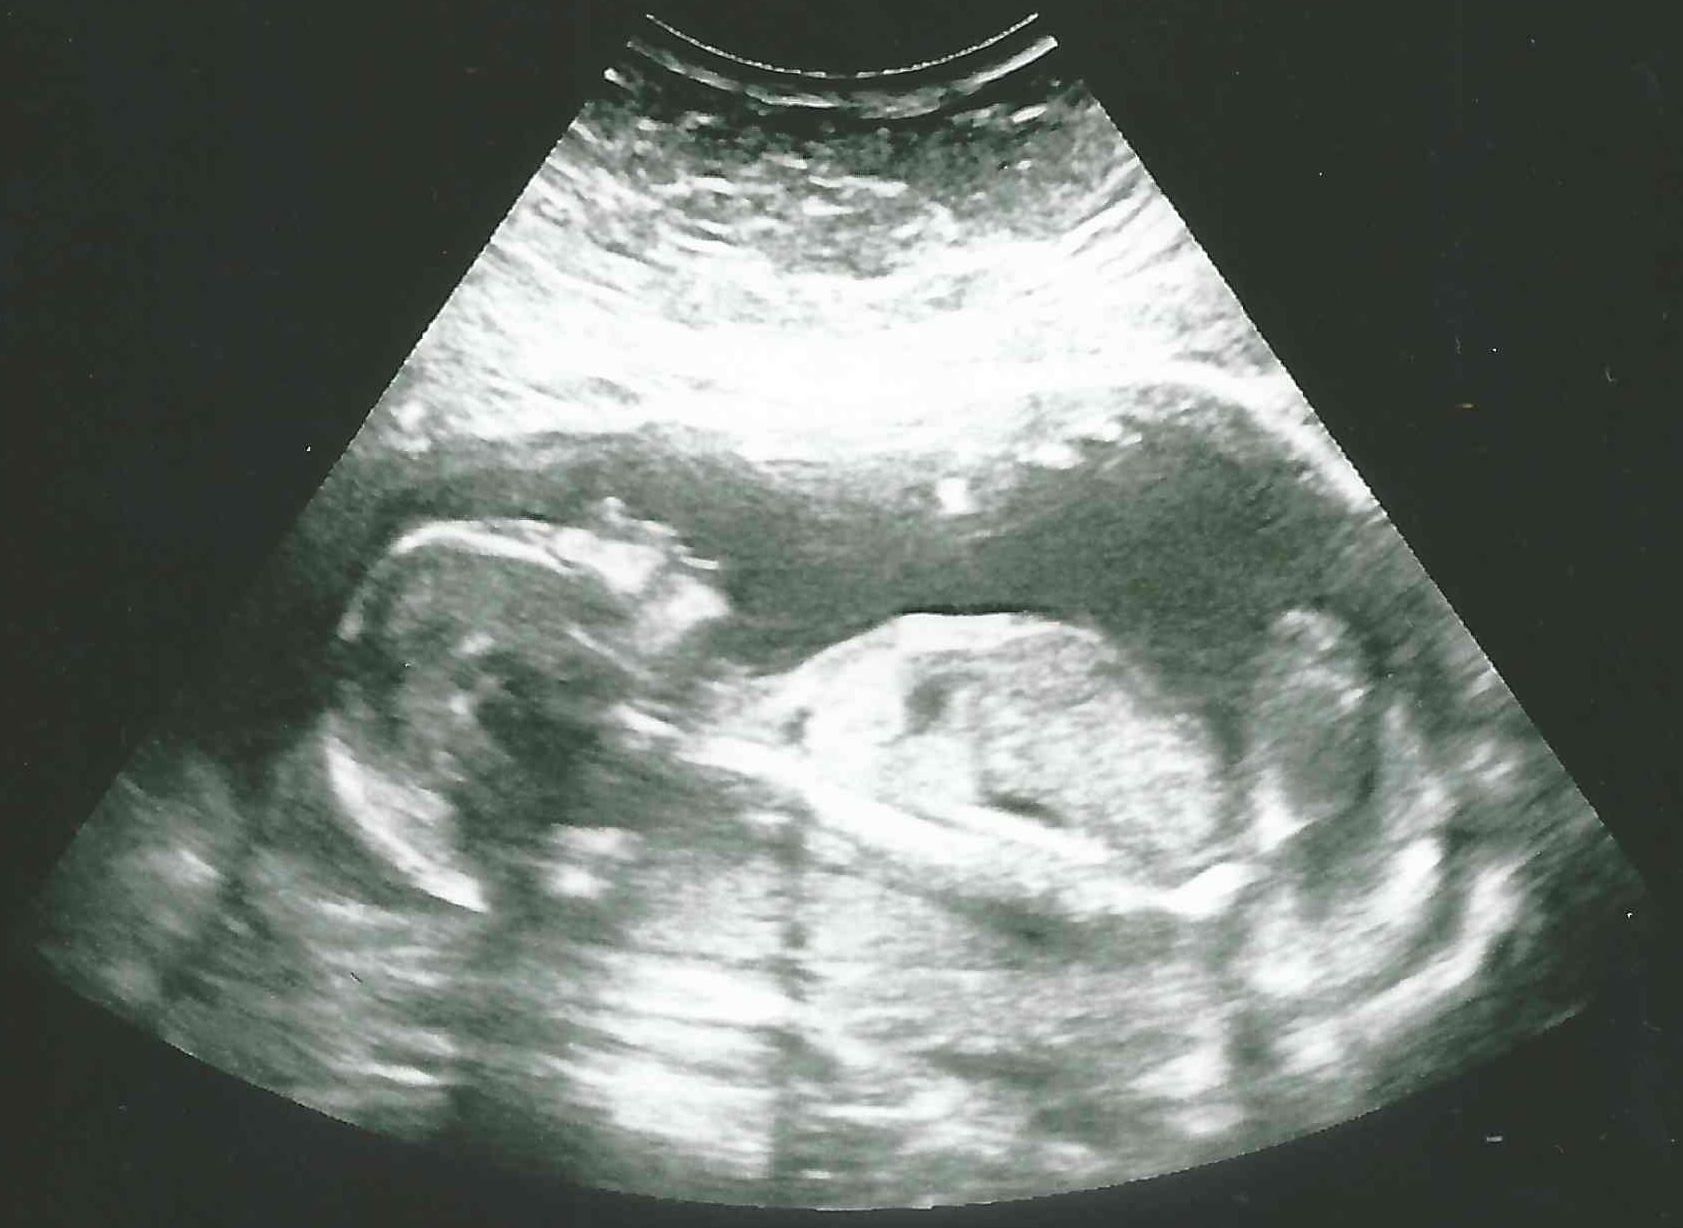

34 weken

Een echo na 34 weken.